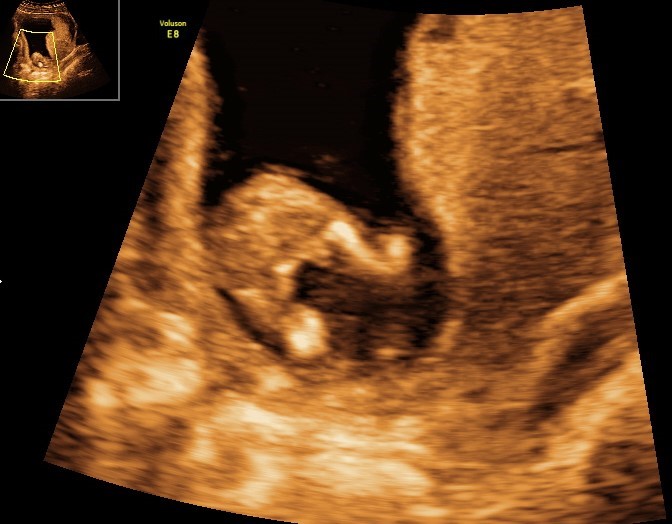

Vores lille bandit ville ingenting da vi var til kønsscanning(14+3), men så lige pludselig var der bare kønsdel på hele skærmen

Vi er i hvert fald ikke i tvivl (selvom hun snød og skrev det på skærmen)